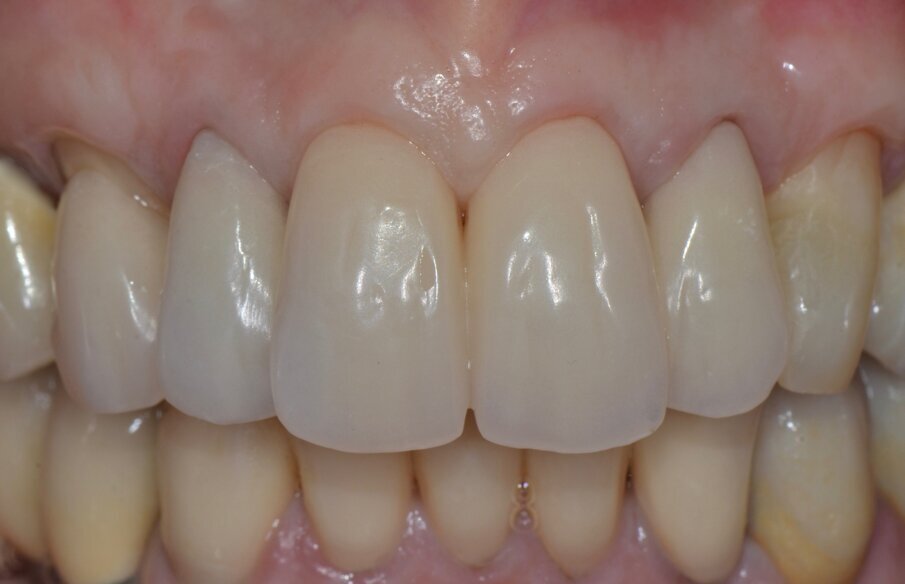

Le corone definitive, come precedentemente descritto, vengono costruite con tecnologia CAD/CAM per una sottostruttura in zirconia di cui viene verificato l’adattamento e ricercata la precisione seguendo gli stessi criteri noti per una prova fusione di una struttura metallica (Figg. 23-29). Dopo la prova le strutture vengono inviate in laboratorio per la stratificazione della ceramica.

La successiva prova clinica è quella delle ceramiche a biscotto durante la quale viene valutata l’occlusione, la fonetica e l’estetica (Figg. 30-33). Durante la stessa seduta viene eseguita la preparazione per la faccetta in disilicato di litio per il canino superiore sinistro che viene rilevata insieme con l’impronta di rimontaggio delle corone superiori. Una faccetta in resina sul canino viene ribasata e solidarizzata al provvisorio superiore (Figg. 34). La settimana successiva i manufatti finiti vengono provati, cementati adesivamente e vengono eseguite le radiografie finali di controllo (Figg. 35-47).